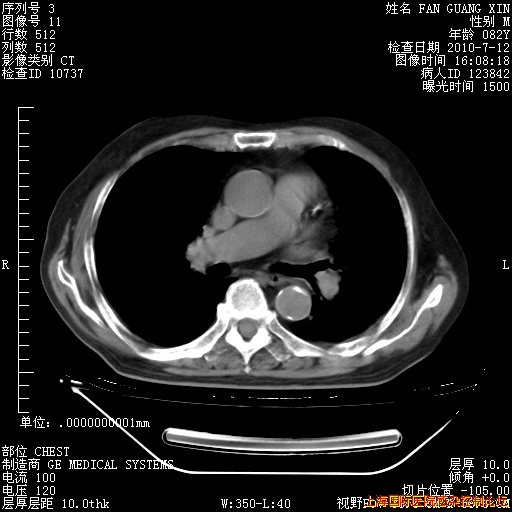

6月12日纵膈窗

今天复查CT

整整相隔30天的肺部CT好像有所好转啊。甲强龙减量第3天,需要观察体温。

海管,自昨日你和我通完话后,不知您岳父消化道症状有无缓解?体温怎样?阅读7.12日胸部ct,个人认为目前激素治疗是有效的,甲强龙减量是适宜的。因在抗痨治疗,需密切观察肝功、肾功能和血常规。不过,老年、长期住院和大量使用激素,很担心菌群失调发生